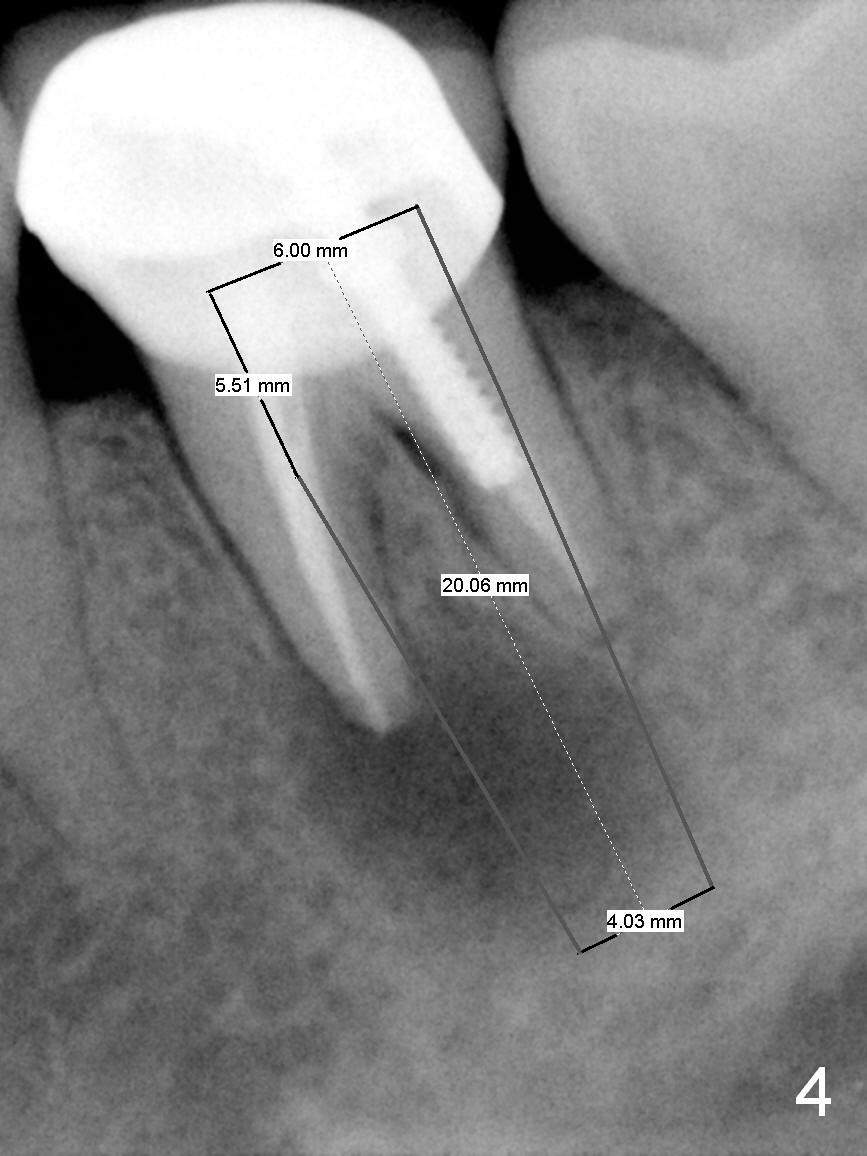

A 58-year-old lady has a long-standing periapical lesion with several episodes of acute infection (Fig.1-3, taken 10, 9 and 2 years ago, respectively). Explore the socket for size and wall integrity (Clindamycin). If the bony defect is not extensive, place a longest implant (18 mm bone-level, 20 mm tissue-level) with moderate diameter (5.5, 6 mm). Otherwise use a shorter, but wider tapered implant (7x12 mm (bone-level), 7 or 8x17 mm (tissue-level)). If the socket is extremely large, consider using 7 or 8 x20 mm cylindrical tissue-level implant. Use Bicon 2 mm pilot drill with extension to measure the socket depth and obtain 3-6 mm new bone or until 20 mm (gingival margin). Take PA. The 1st option is to use UF 3-4.7x18 mm drills at 50 RPM. Make sure that the depth is reached (septum crestal level) and check osteotomy wall integrity after each drill. Then place a 5 or 5.5x16 or 18 mm implant (Fig.6). The 2nd and 3rd options are shown in Fig.4 and 5. Due to severe infection and pain, a shorter implant is placed.